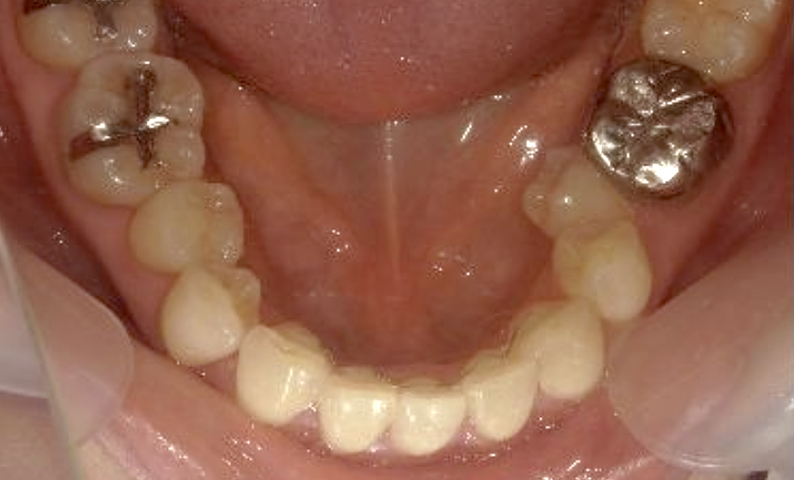

症例_002 下顎だけの部分矯正

治療期間:6ヶ月金額:21万円+税女性前歯のデコボコ下の前歯だけ

| Before | After |